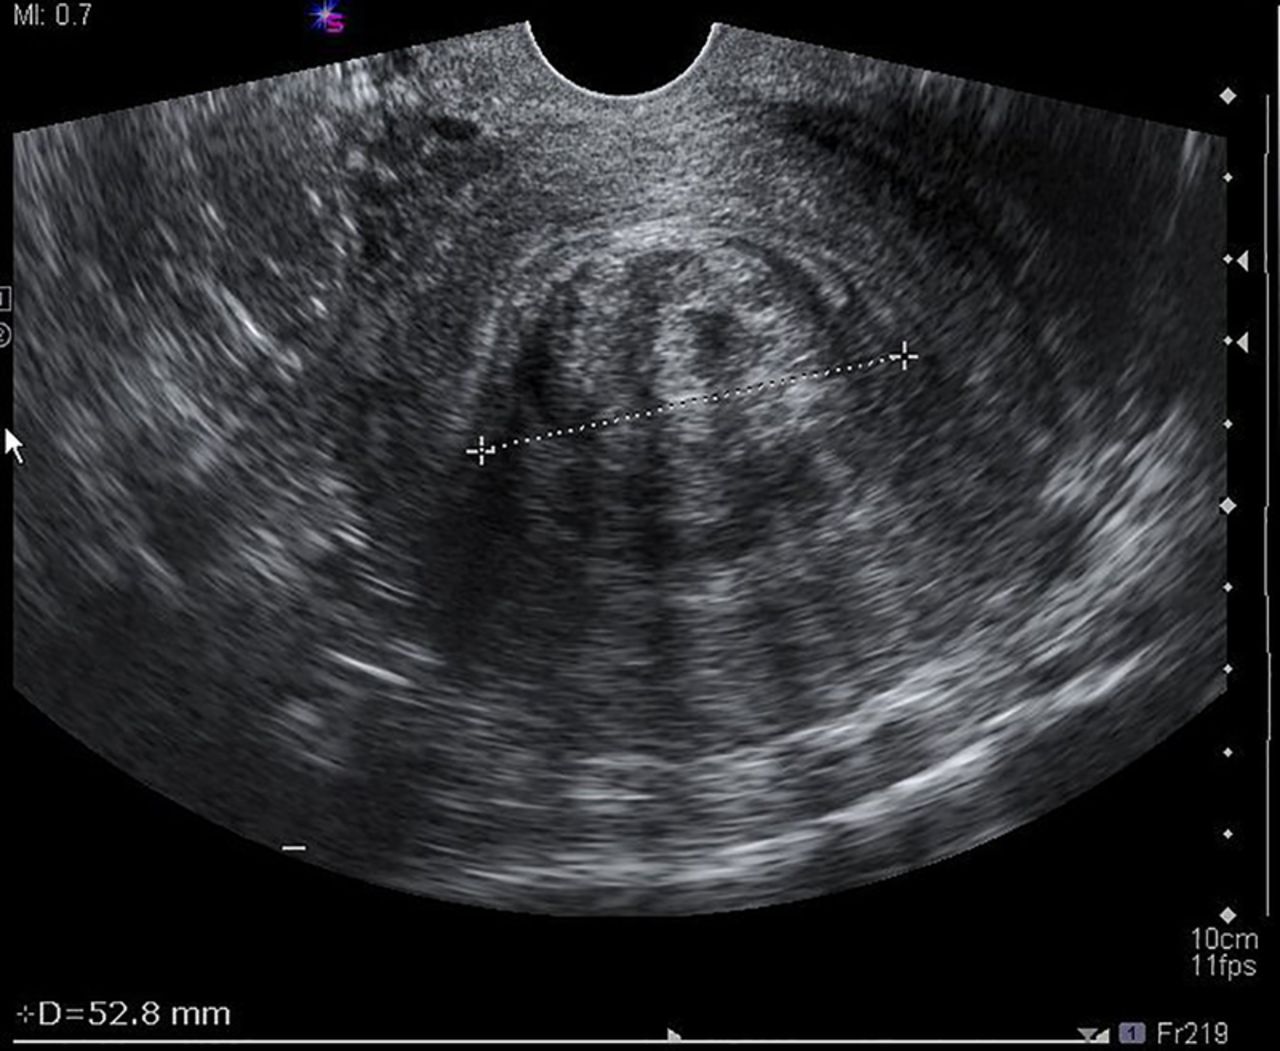

The woman, who has been battling fibroids for several years, says the condition has steadily worsened, affecting her health, daily life, and fertility. Fibroids are non-cancerous tumours that grow in and around the uterus and are known to disproportionately affect Black women. In her case, the growths have caused chronic pain, heavy bleeding, and increasing concern about long-term reproductive damage.

After seeking medical advice locally in St Vincent and the Grenadines, she was advised that specialised surgical care was not readily available and that treatment abroad was necessary. Like many Vincentian women facing similar diagnoses, she has been forced to look to Barbados for treatment.